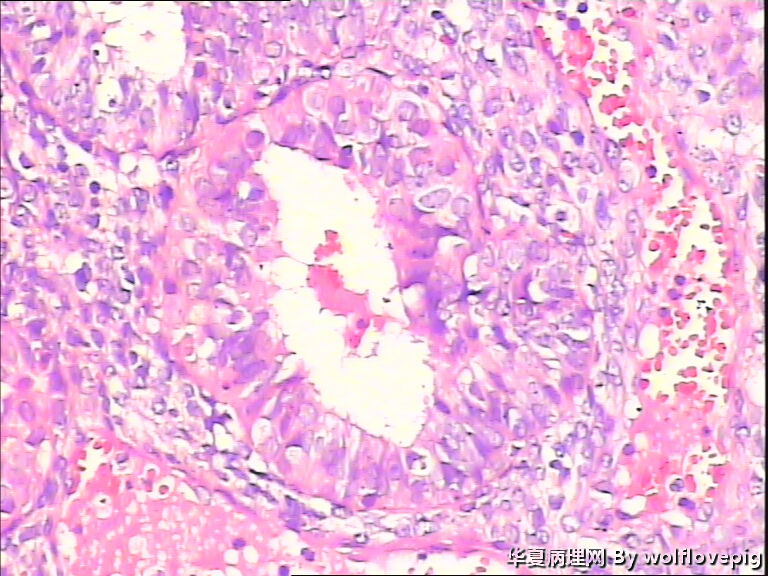

求助,子宫内膜!

48y

• 求助,子宫内膜!图4

图4

子宫内膜复杂性非典型增生(有没有癌变,待制作优良的切片再诊断吧)。